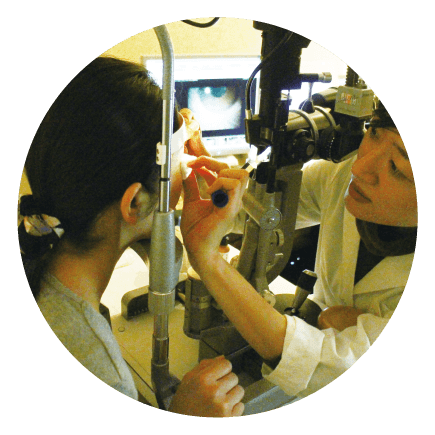

03 スリット顕微鏡で診察

IPL照射後のマイボーム腺を観察します